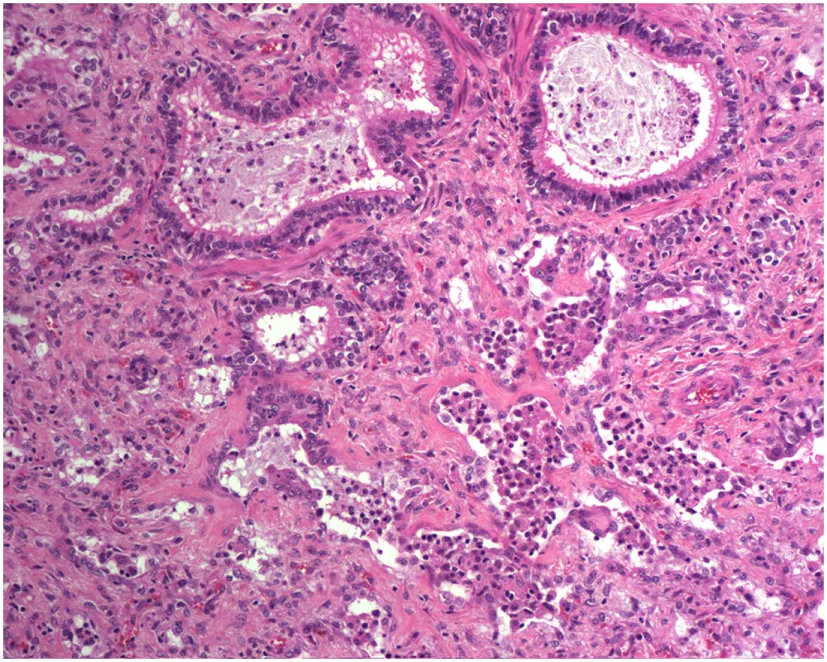

A study on Westies (109) found that the majority of dogs with IPF showed multifocal areas of accentuated subpleural and peribronchiolar fibrosis with occasional “honeycombing” and profound alveolar epithelial changes, reminiscent of human UIP and not commonly seen in NSIP. Interstitial fibroblastic foci, characteristic of UIP, were not seen in WHWTs with IPF. Progressive fibrosis, with intra-alveolar organizing fibrosis alongside interstitial mature collagen deposition, was present within the more severely affected areas of lung in WHWTs with IPF. Severe pulmonary lesions were seen more commonly in the caudal than in the cranial lung lobes.

The authors acknowledge the Lester and Sue Smith Foundation, Coalition for Pulmonary Fibrosis, and the Pulmonary Fibrosis Foundation for their support. The authors also acknowledge Amy Miele, BVM&S MRCVS (University of Edinburgh) for her contributions in providing veterinary histopathology images used in the construction of Table 1. AT is a recipient of a Marie Curie/Sklodowska ERS/RESPIRE 2 fellowship (8860-2015). All authors have no financial affiliations or conflicts of interest to disclose.